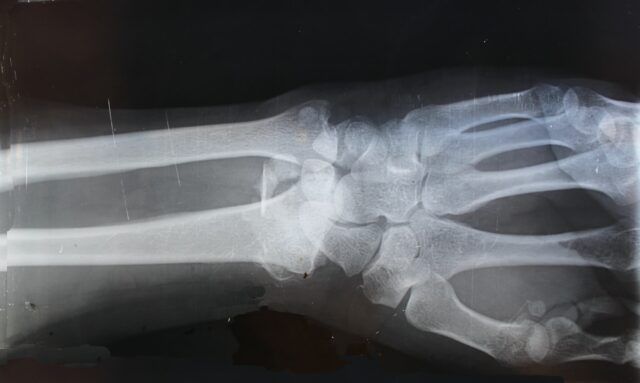

Inteligența artificială (AI) are efecte benefice asupra muncii radiologilor, care consumă extrem de mult timp cu interpretarea investigațiilor radiologice.

Un studiu publicat în Academic Radiology detaliază modul în care experții au reușit să reducă cu aproximativ 40% din timpul de interpretare a radiologilor utilizând un instrument de învățare profundă pentru a identifica imaginile relevante anterioare ale pacienților.

Nu numai că instrumentul AI TimeLens a fost eficient în identificarea examenelor, dar a semnalat și constatările de interes din examenele anterioare pentru a fi examinate de radiologi.

TimeLens se bazează pe procesarea limbajului natural și pe algoritmi de potrivire a imaginilor bazați pe descriptori. Echipa a evaluat timpii și obiceiurile de interpretare a cititorului (clicuri, mișcări ale mouse-ului etc.) atunci când a folosit instrumentul pe 3872 serii de 246 de examinări radiologice de la 75 de pacienți (189 CT, 95 RMN).

Utilizarea sa a redus timpul mediu necesar pentru a examina o descoperire de la 107 secunde la 65 de secunde, evaluările nodulilor pulmonari beneficiind de cele mai mari reduceri. Deoarece instrumentul a identificat antecedente relevante pentru cititori, utilizarea sa a redus, de asemenea, clicurile cu mai mult de 17% și mișcările mouse-ului cu 38%.